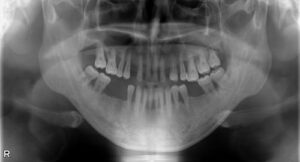

• 上下顎オールオン6症例

BEFORE AFTER 63歳男性/上顎6本・下顎6本 【治療内容】 全体的に歯が揺れてお食事がとりづらくなり、来院さ…